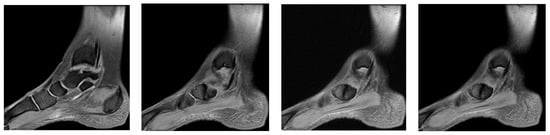

3.4. Case 4: Type III Accessory Navicular Impingement

A 26-year-old goalkeeper with a navicular injury, boasting six years of experience as a first-league professional in Romania, hails from an urban area and stands at 192 cm, weighing 95 kg. The latest case involves this goalkeeper, who, after sustaining a direct contact trauma during a match, reports experiencing pain and swelling in the dorsal part of his right forefoot. Forefoot X-ray diagnoses an improperly healed old right navicular fracture. As there was no trauma of the right foot, an MRI was performed, confirming the diagnosis of type III accessory navicular bone with impingement on the posterior tibial tendon.

Ankle MRI showed a well-delimited oval formation, at the posterior part of the navicular, with similar signals to the latter in T1 and T2 ponderations (bone formation), establishing certainty diagnosis of accessory navicular bone, excluding the suspicion of improperly consolidated navicular fracture/pseudoarthritis. STIR and PD fat sat sequences reveal hypersignal alterations in the posterior tibial tendon tangent to the accessory bone mentioned above, establishing the diagnosis of impingement syndrome with subsequent tendinopathy alterations (Figure 9, Figure 10 and Figure 11).

Figure 9.

(a) Ankle MRI: sagittal stir acquisition, (b) ankle MRI: sagittal stir acquisition, (c) ankle MRI: axial T2 acquisition, (d) ankle MRI: sagittal T2 fat sat acquisition, (e) ankle MRI: coronal PD fat sat acquisition, (f) ankle MRI: coronal T1.

Figure 10.

(a) Ankle MRI: axial T2 acquisition, (b) ankle MRI: axial T2 acquisition, (c) ankle MRI axial T2 acquisition.

Figure 11.

Ankle MRI: sagittal T2 fat sat acquisition.

Excluding the improperly healed fracture of the navicular, the patient was treated as a contusion with functional rest, NSAIDs, analgesics, and physical therapy, which allowed the player to recover early and resume his competitive activity after 1 week.